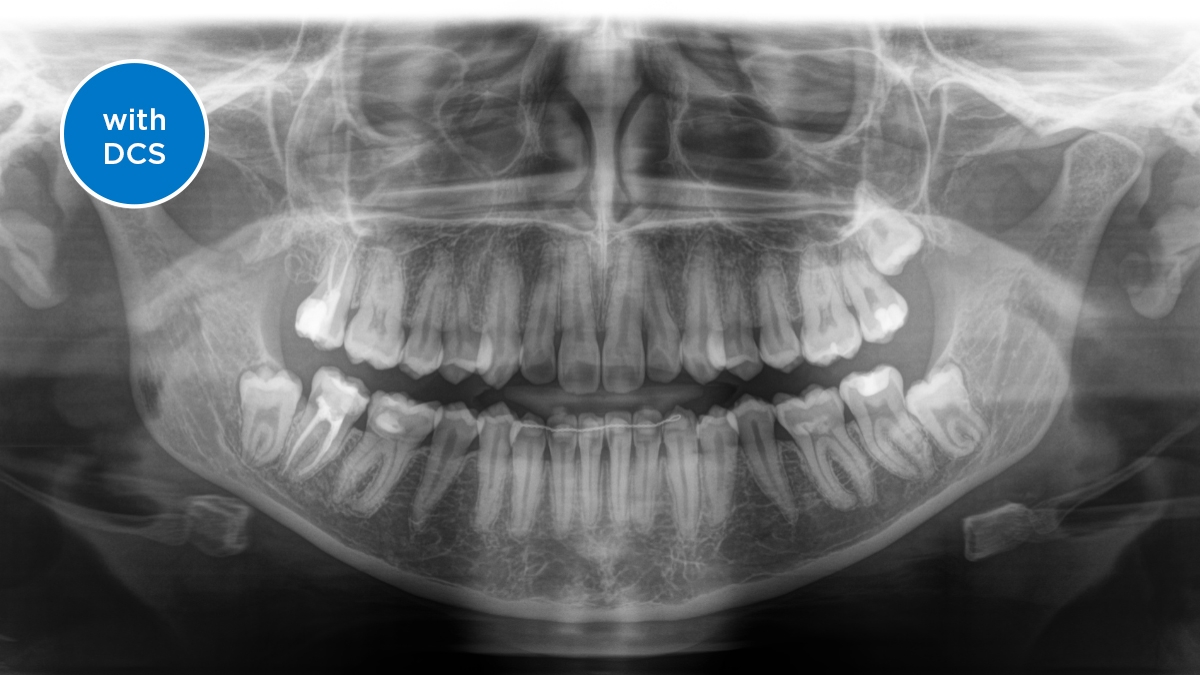

Senzor s přímou konverzí (DCS)

DCS přeměňuje rentgenové záření na elektrický signál, aniž by došlo ke ztrátě informace. DCS senzor vytváří maximálně ostré panoramatické rentgenové snímky s vysokým kontrastem a ve výjimečné kvalitě.

Senzor s přímou konverzí (DCS): ostrý snímek

Direct Conversion Sensor (DCS - senzor s přímou konverzí) přinesl revoluci do standardů panoramatického zobrazování. Rentgenové snímky jsou přeměňovány přímo na elektrický signál. Nedochází ke ztrátě signálu v důsledku konverze světla jako je tomu u běžných systémů. Výsledkem jsou snímky s extrémně vysokou a vysoce kontrastní úrovní ostrosti i při velmi nízké dávce záření. Pro jasnou diagnózu a mnohem lépe cílenou léčbu.

Obrázek ukazuje RTG snímek s a bez použití DCS technologie. Přejeďte si středovou linkou po obrázku a uvidíte co DSC senzor dokáže udělat s kvalitou snímku.